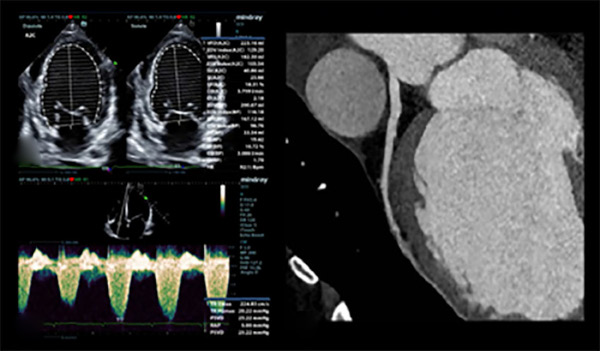

Figure 2

Cardiac magnetic resonance imaging with gadolinium-based contrast agent showing mid-myocardium delayed enhancement pattern involving the junction site between right and left ventricular myocardium and anteroseptal and inferoseptal segments, and subepicardial enhancement of the anterolateral and inferolateral segments.

The indications in the CCU included negative fluid balance, levosimendan pulses and complete medical treatment for advanced heart failure. During hospitalization an echocardiogram was performed with measurement of ventricular strain (-14%). There were no coronary artery lesions on coronary computed angiotomography with coronary calcium scoring. Cardiac magnetic resonance imaging (MRI) with gadolinium-based contrast agent demonstrated dilated cardiomyopathy with mid-myocardial delayed enhancement pattern involving the junction site between the right and left ventricular myocardium and anteroseptal and inferoseptal segments, and subepicardial enhancement of the anterolateral and inferolateral segments, a pattern also described in other entities such as idiopathic dilated cardiomyopathy and myocarditis. In addition, a 24-hour Holter monitoring was ordered, which only evidenced infrequent atrial premature contractions. After six days of hospitalization, the patient was discharged with indication for referral to a heart transplant center on an outpatient basis.